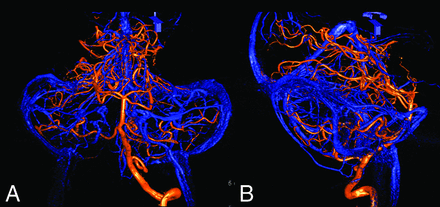

3) In a man presenting with Moyamoya disease, full arterial and venous angiography was performed for surgical planning in anticipation of a possible direct bypass. As part of the cerebral angiogram, a vertebrobasilar AV-3D-DSA was obtained (Fig 3).

Frontal (A) and lateral (B) fused AV-3D-DSA of left vertebral artery injection demonstrating well the relationship between the petrosal veins and the vertebrobasilar system.